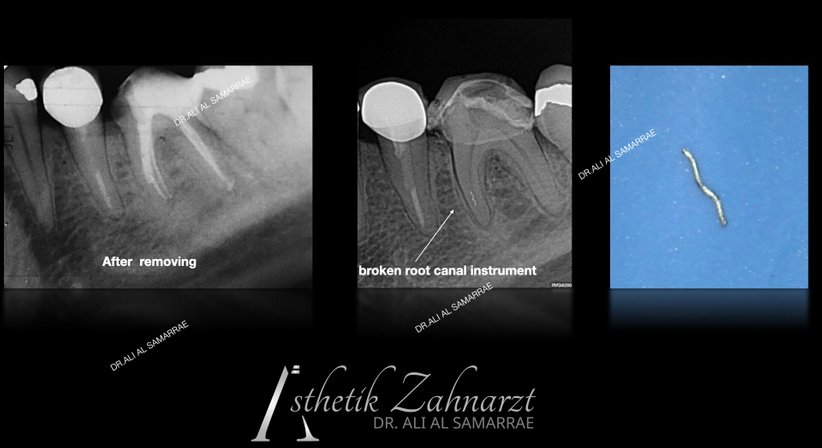

1 – Der Endodontist bzw. Mikroskopzahnarzt untersucht den Zahn und erstellt Röntgen. Unter Anästhesie, wenn gewünscht, wird dann gearbeitet. Wenn möglich wird ein sogenannter „Kofferdam“ über den Behandlungsbereich gelegt, um den Zahn zu isolieren und ihn während des Eingriffs sauber und speichelfrei zu halten.